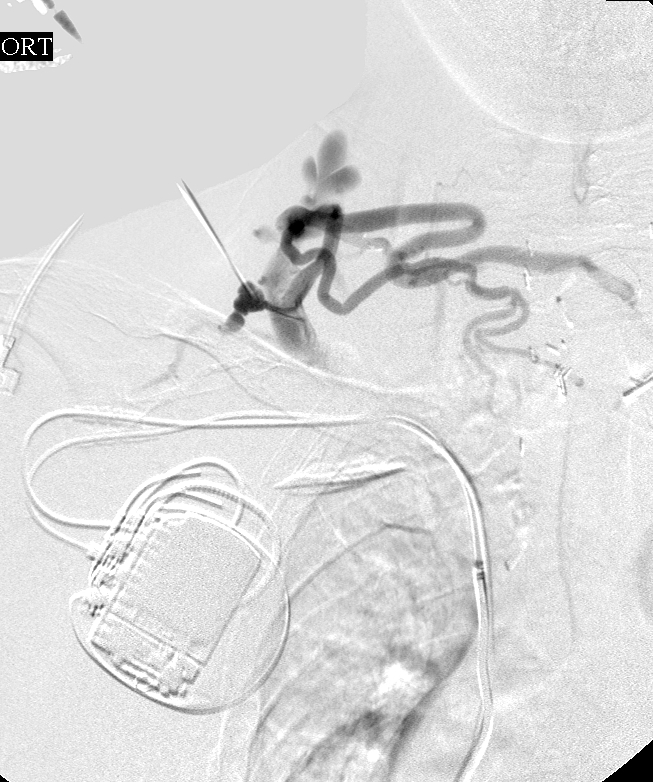

Central venogram through the right external jugular vein (REJV): There is chronic total occlusion of the distal REJV.